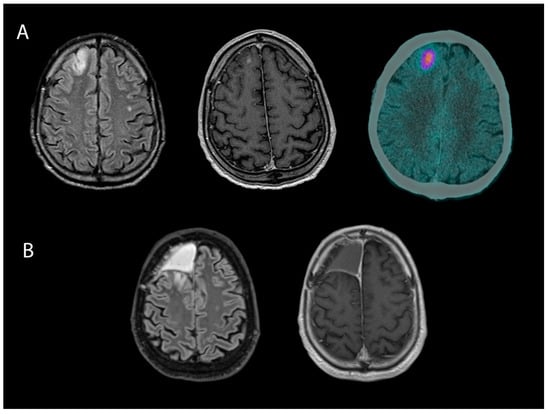

- Ninatti, G.; Sollini, M.; Bono, B.; Gozzi, N.; Fedorov, D.; Antunovic, L.; Gelardi, F.; Navarria, P.; Politi, L.S.; Pessina, F.; et al. Preoperative [11C]methionine PET to personalize treatment decisions in patients with lower-grade gliomas. Neuro-Oncology 2022, 24, 1546–1556. [Google Scholar] [CrossRef] [PubMed]

- Bono, B.C.; Ninatti, G.; Riva, M.; Raspagliesi, L.; Barbieri, E.M.; Navarria, P.; Clerici, E.; Politi, L.S.; Simonelli, M.; Rodari, M.; et al. The role of preoperative [11C]methionine PET in defining tumor-related epilepsy and predicting short-term postoperative seizure control in temporal lobe low-grade gliomas. Neurosurg. Focus 2024, 56, E6. [Google Scholar] [CrossRef]